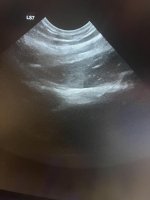

Hi ich arbeite mit Tieren und hatte beim halten eines Tieres mich am Oberarm verletzt. Eine ruckartige Bewegung durch einen Hund hat mir stechende Schmerzen beschert … immer wieder kommen sie . Arm naxh Belastung bzw anwinkeln schmerzhaft zwischendrin. Erstaunlicherweise kein Hämatom . Aber über sono sagt meine Kollegin dass das Bindegewebe verdickt sei und an einer Stelle naxh einen kleinen Riss aussieht.

Sieht jmd das hier evtl auxh ?